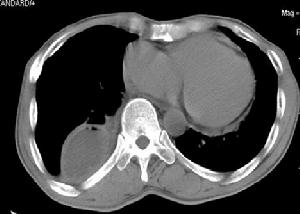

1、X 線胸片 少量積液可僅表現為患側肋膈角模糊、變鈍或消失;中等量積液可見患側下胸部大片均勻的緻密陰影,上緣呈外高內低的弧形;大量積液時患側胸部呈大片均勻的緻密陰影,氣管和縱隔對側移位,患側膈肌下移;包裹性積液表現為大小不等的圓形或半圓形均勻的緻密陰影,邊緣光滑清晰;葉間積液在側位片上呈長軸與葉間裂一致的邊緣銳利的梭狀均勻的緻密陰影;肺底積液在正位片上易與膈肌升高混淆,患側臥位透視或拍片則可見膈肌水平正常,胸水沿下側胸壁分布。X 線檢查不僅可以診斷積液,而且有助於原發病的診斷。

2、CT 和MRI 檢查 CT 和MRI 具有對密度分辨力高和二維圖像的特點,可以很好地區分液體與實體影,能很好地顯示X 線平片盲區的小病灶或少量積液,能突現出被胸水掩蓋的肺內塊影,還有助於區分積液的性質。